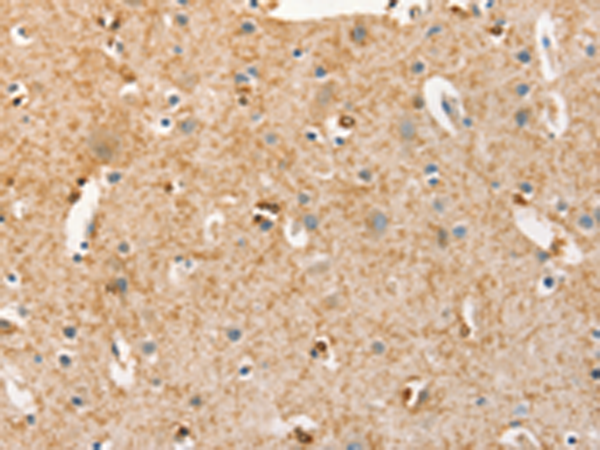

分类: 科研抗体货号: P07106别名: BBS3, RP55应用: IHC反应种属: Human, Mouse